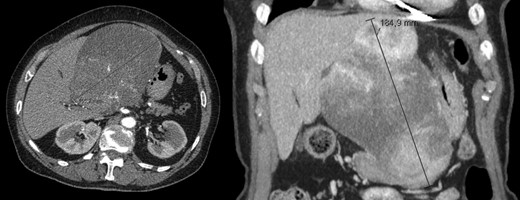

A 78-year-old woman with past medical history of hypertensive cardiopathy and bearer of a pacemaker, was referred to our Hepatobiliary Unit with diagnose of a liver mass discovered on CT scan, which was performed after complaints of nausea and postprandial infarction. CT scan (Fig. 3) showed a voluminous heterogeneous, lobed mass, displaying heterogeneous uptake contrast, relatively vascularized, localized in segment 1, with exophytic growth to the left lobe, with 18.5 × 13.8 × 15.6 cm; the tumor caused deviation of the stomach to the left.

AP-CT – voluminous heterogeneous mass in segment 1 with 18.5 cm in diameter.